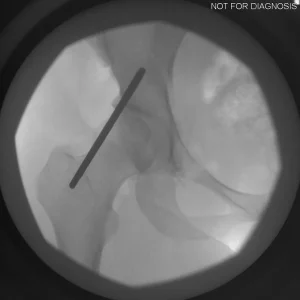

The Surgery

• PAO surgery typically takes 2-4 hours

• It is performed under general anesthesia

• Several controlled bone cuts are made around the hip socket

• The socket is repositioned and fixed with screws

• The hip joint itself is preserved